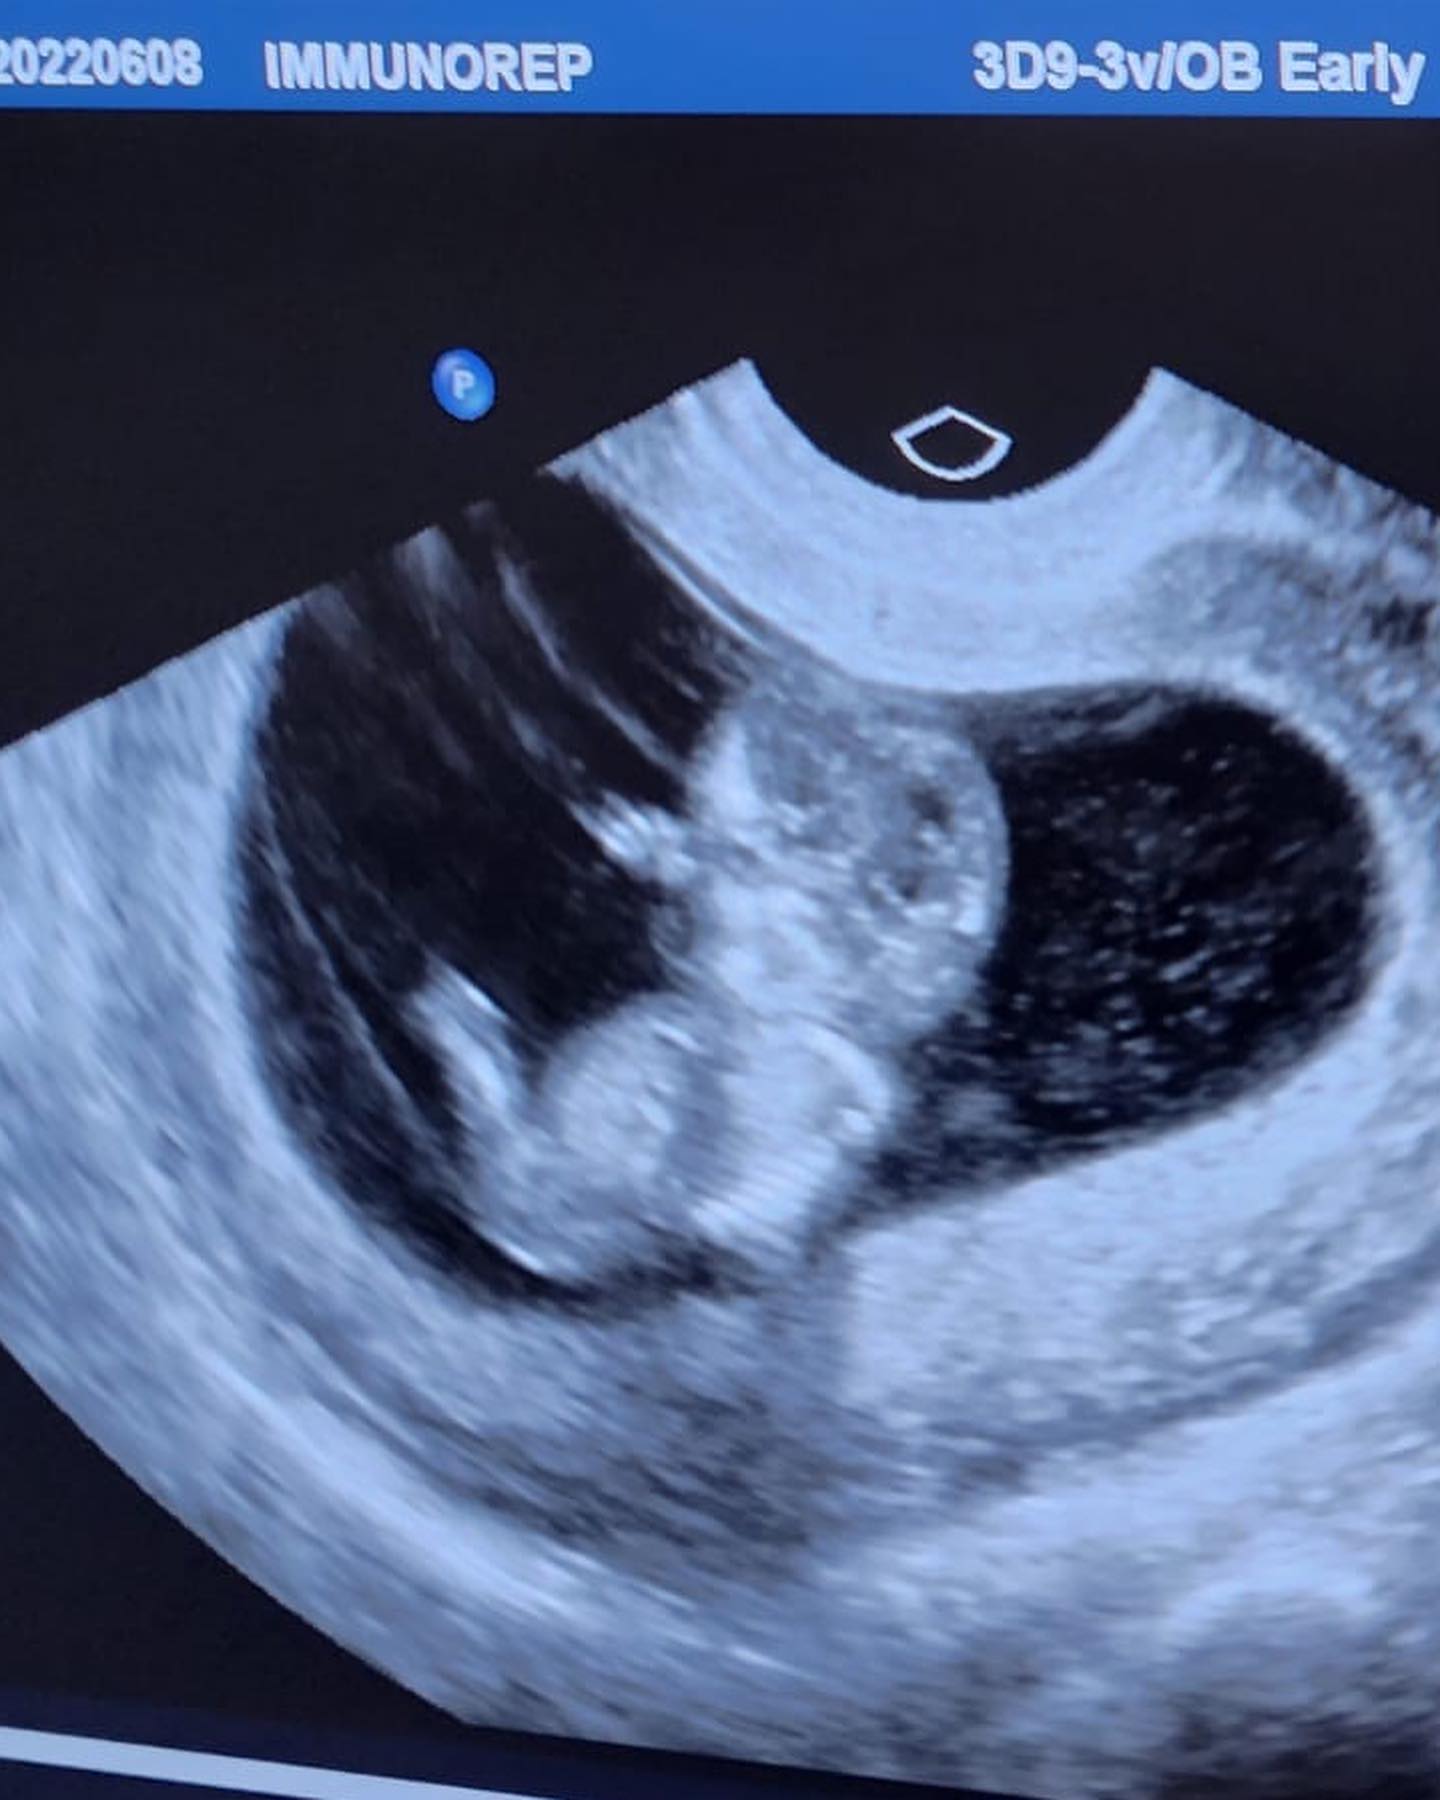

¿Es neta?”, le preguntó Paul Stanley, al tiempo que enviaron a una cápsula en la que Andrea Escalona explica que tiene 13 semanas de embarazo.

Tengo 13 semanas, todo está bien, ha sido algo super bonito que todavía no me lo creo y efectivamente, estoy embarazada, vamos a ser tíos, bueno, ustedes, yo voy a ser mamá, aquí”, dijo Andrea Escalona desde el consultorio médico.